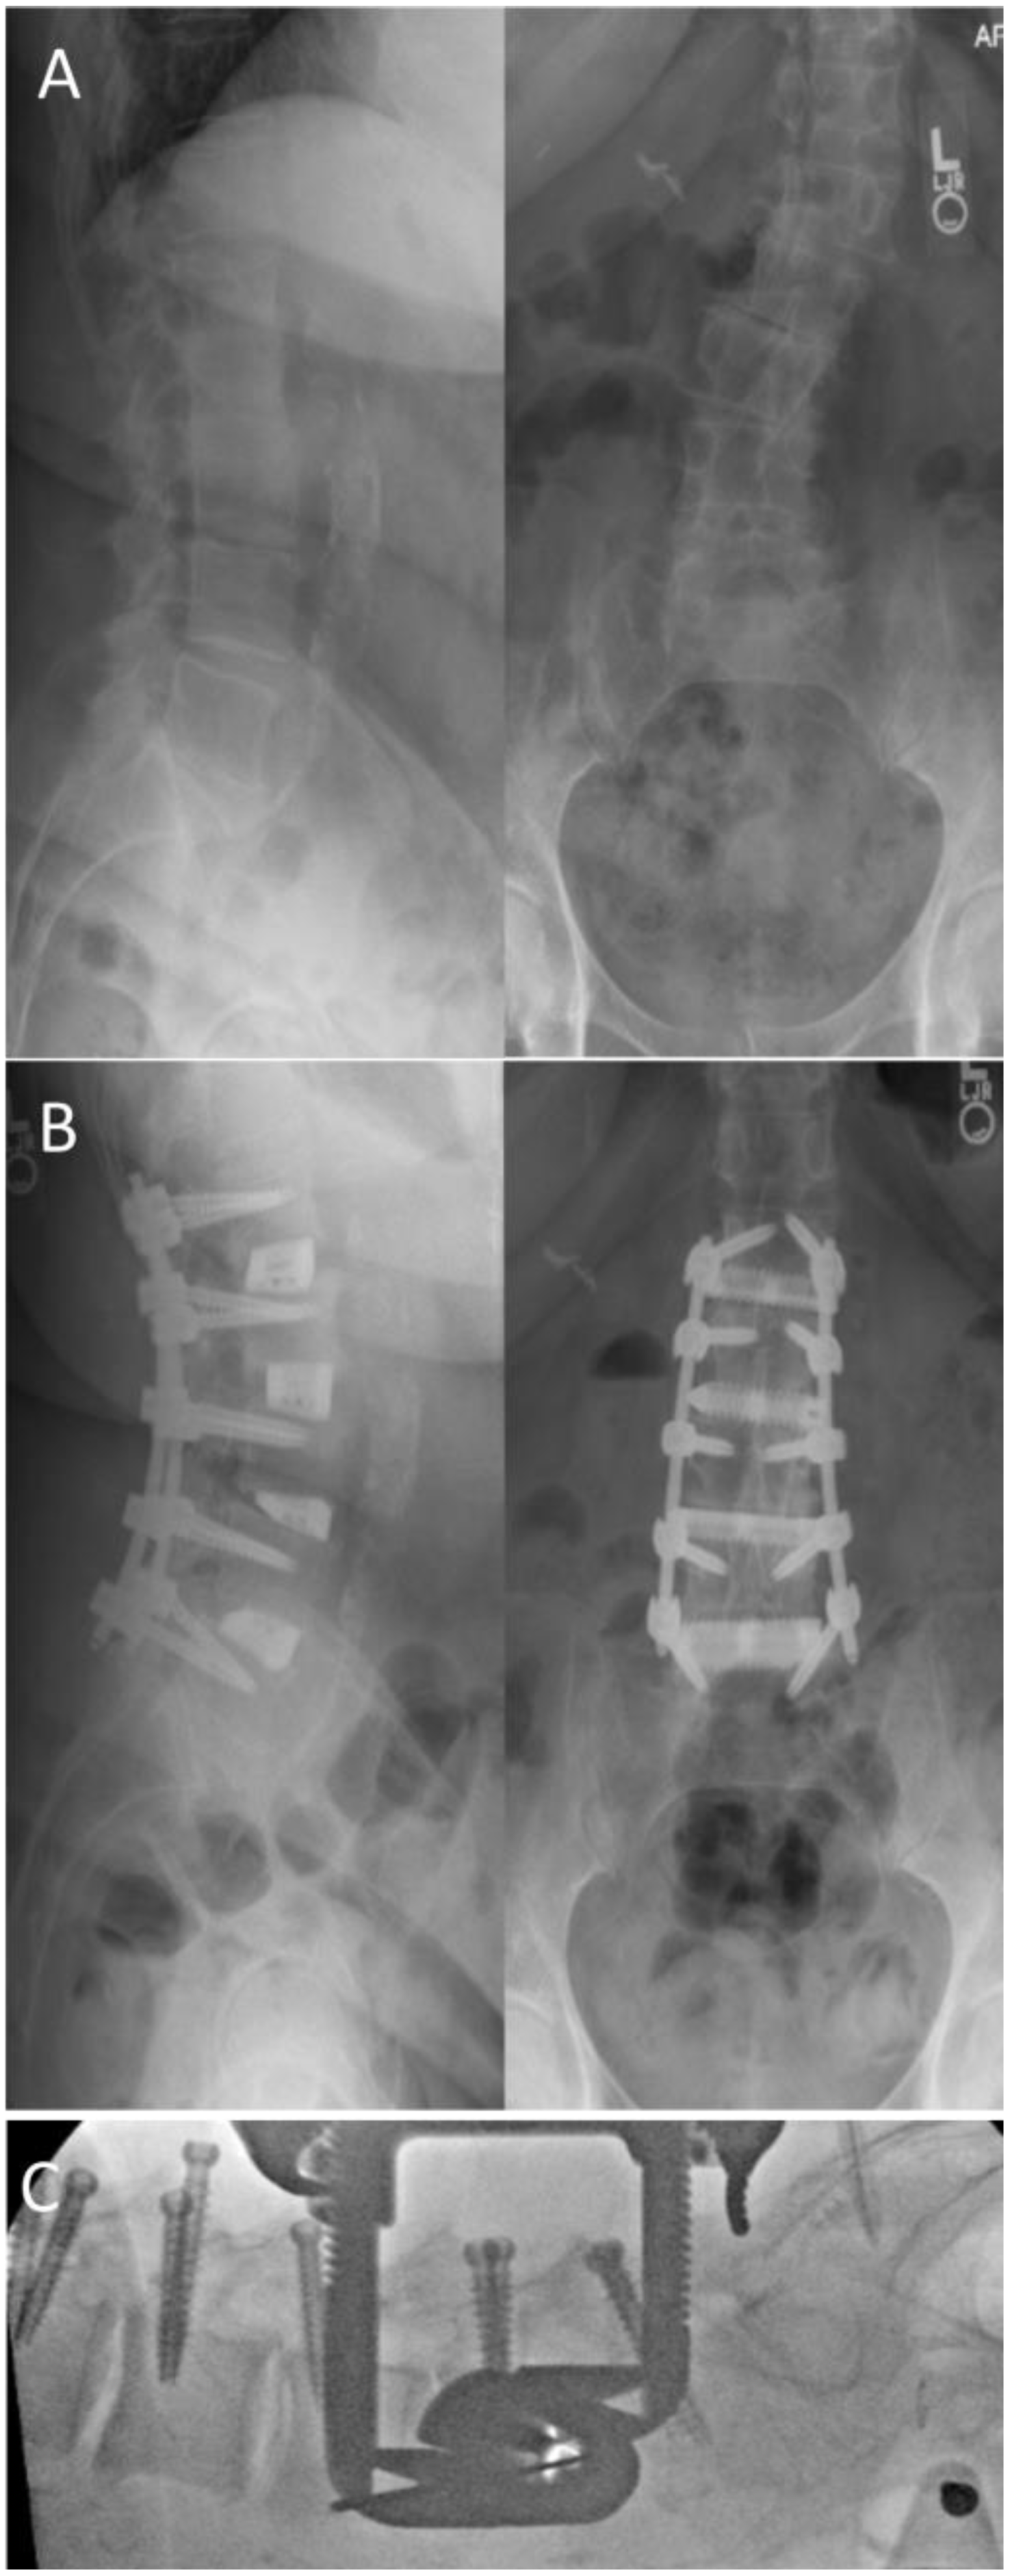

4.2. Case 2